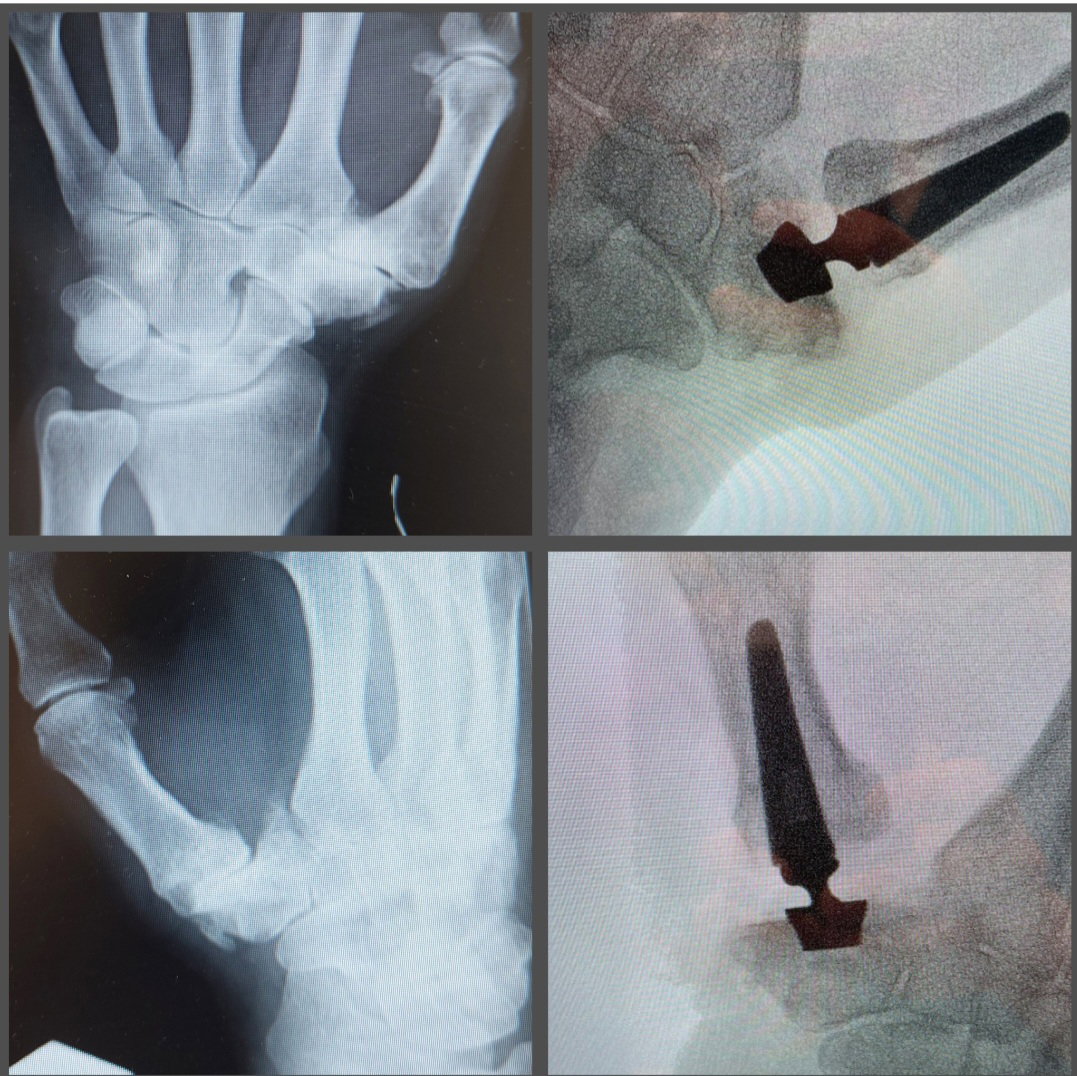

3. צילום רנטגן בו ניתן לראות את סימני השחיקה של המפרק.

NSAID'S .2. ניתוחי: # ישנם מספר סוגי ניתוחים משחזרים לטיפול בדלקת בבסיס האגודל ויש להתאים לכל מצב פרטני את הניתוח המתאים לו. סוגי ניתוחים הכי שכיחים:

1. החלפת מפרק ללא שתל ארטרופלסטיה

2. טרפזיקטומיה -כריתת העצם באופן מלא או הימטרפזיקטומיה - כריתה חלקית של עצם הטרפיזיום

3. החלפה מלאה של המפרק - שתל מלאכותי .